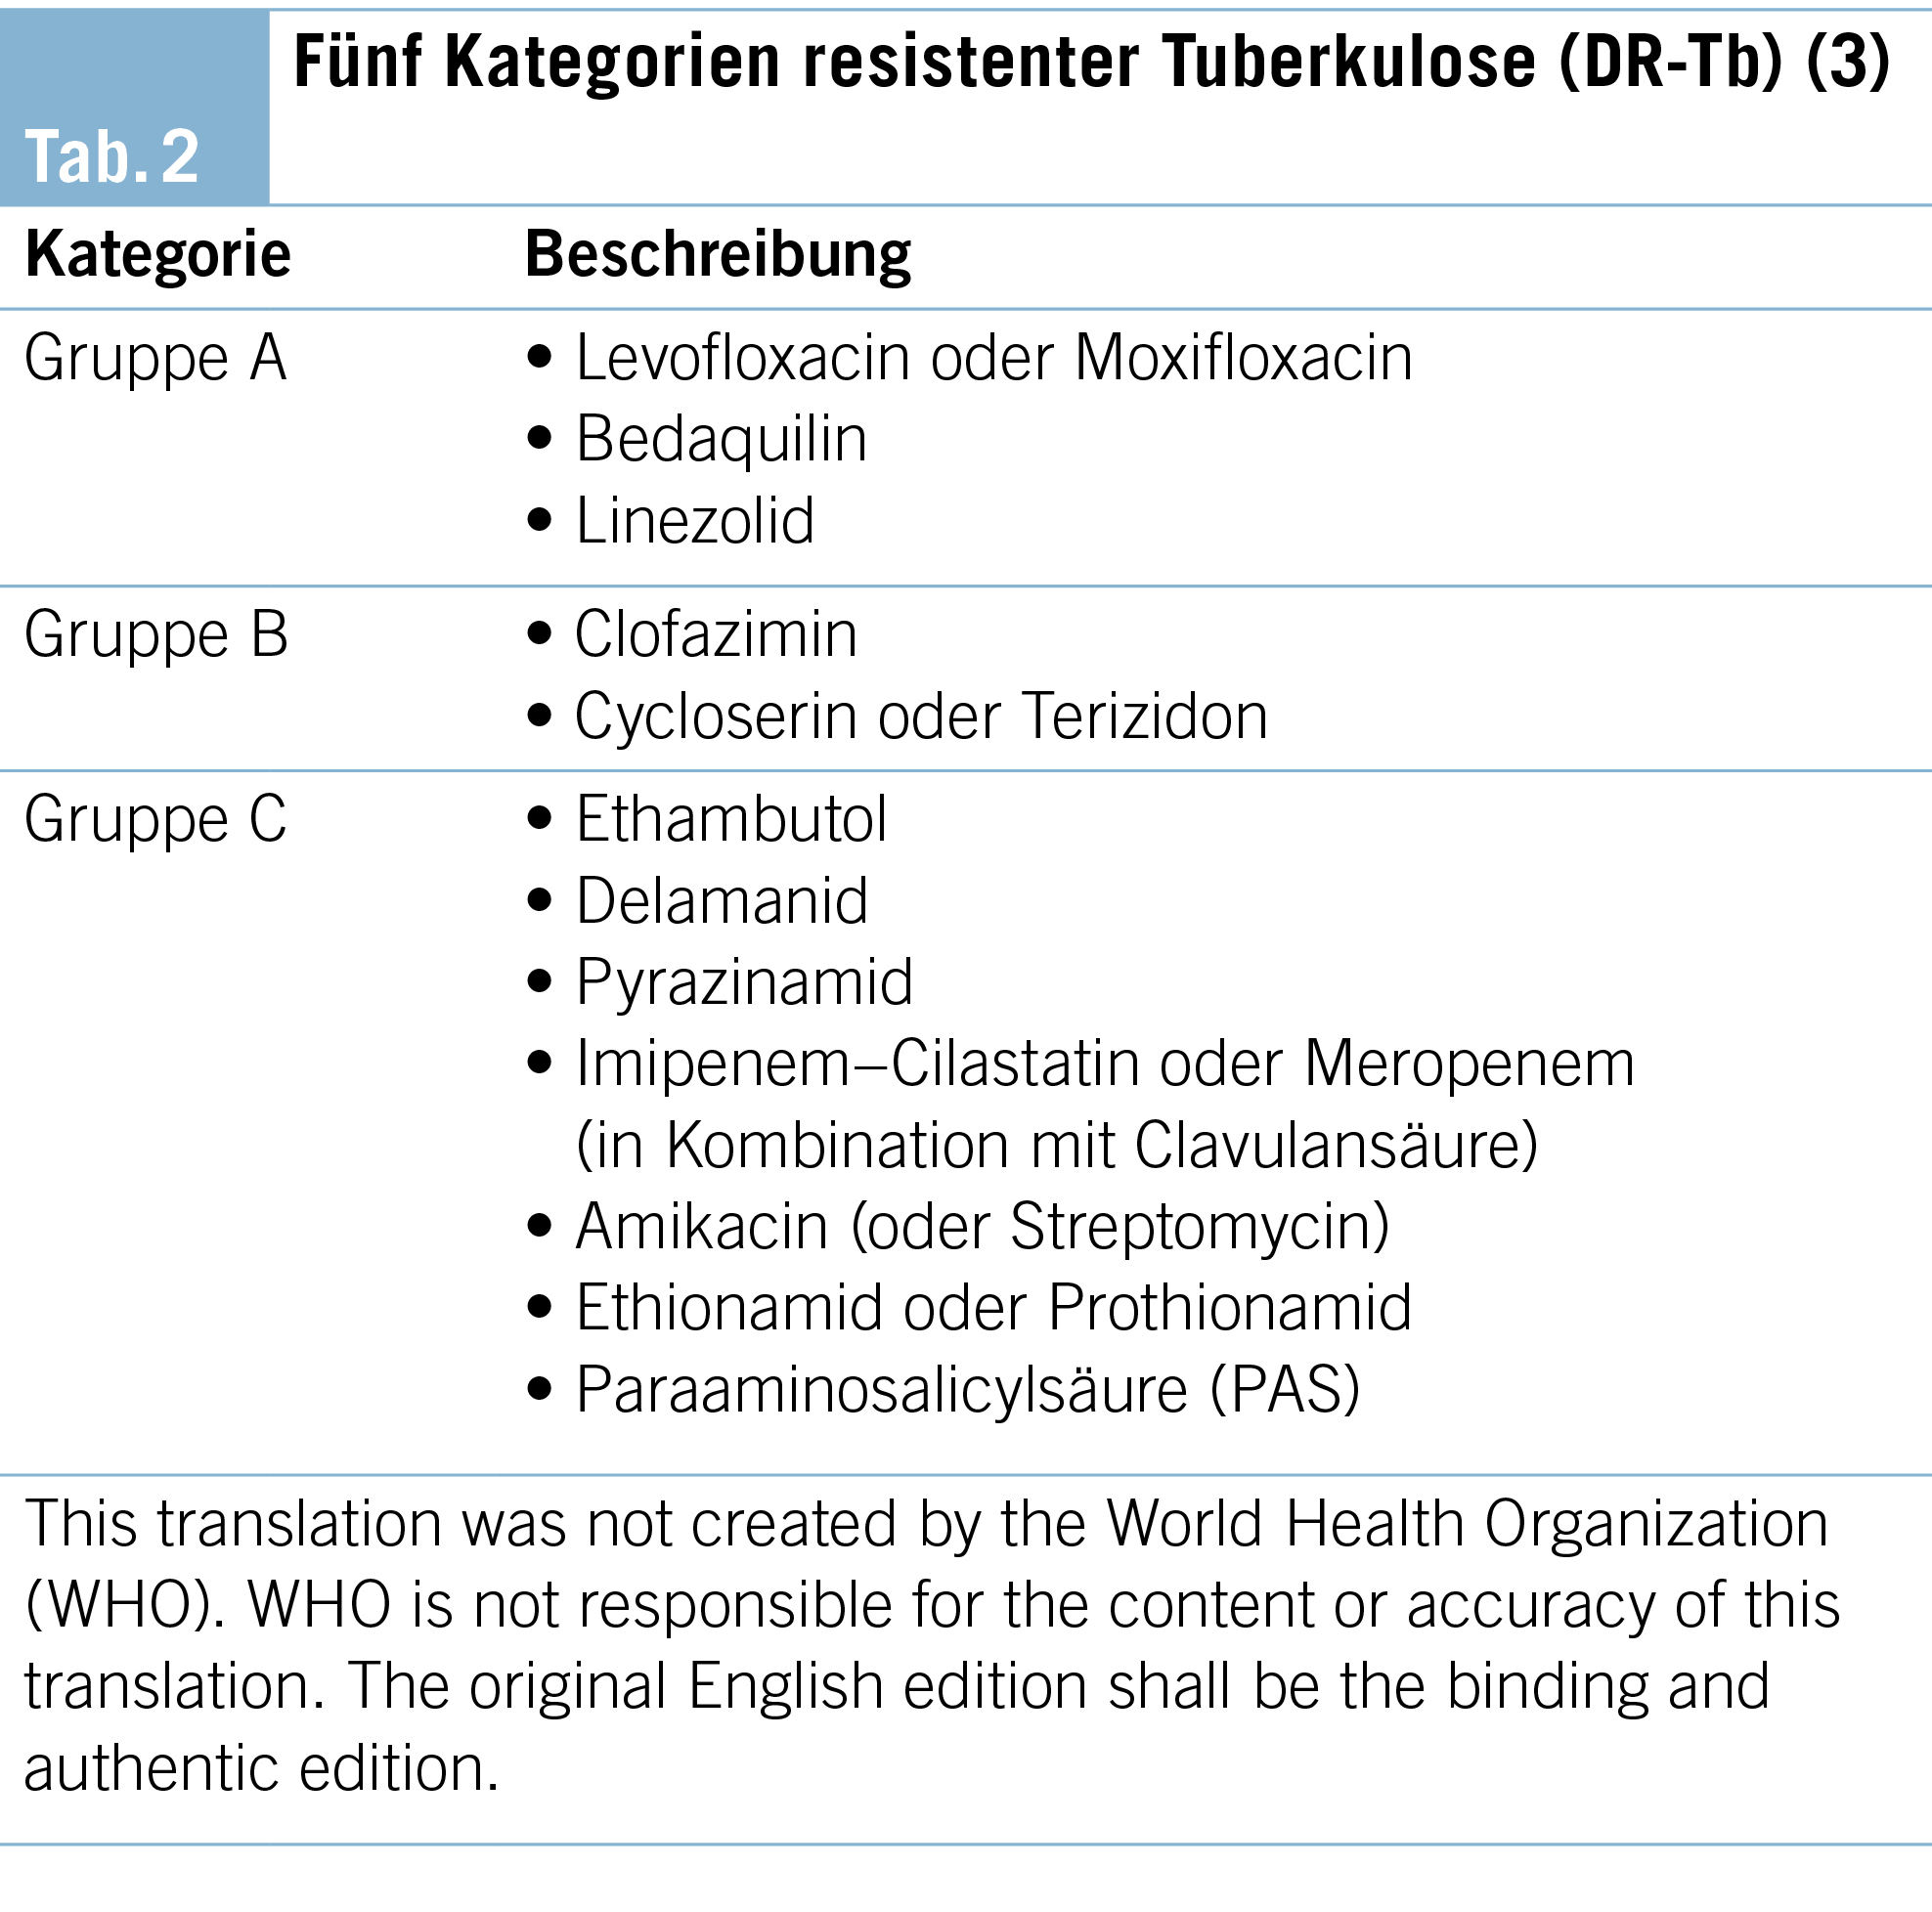

Diese Zweitlinienmedikamente wurden von der WHO in die drei Gruppen A, B und C in absteigender Hierarchie nach Wirksamkeit, Sicherheit und Einfachheit in der Anwendung eingeteilt (Tab. 2). Die Therapie soll zusammengesetzt werden aus mindestens vier ‘wahrscheinlich wirksamen’ Medikamenten, nach Möglichkeit soll eine Kombination von drei Substanzen der Gruppe A und mindestens einer Substanz der Gruppe B gewählt werden. Wenn keine vier ‘wahrscheinlich wirksamen’ Medikamente in den Gruppen A und B vorhanden sind (bei Vorliegen von Resistenzen oder Intoleranzen), sollen welche der Gruppe C eingeschlossen werden. Die Therapiedauer beträgt 18–20 Monate (10).